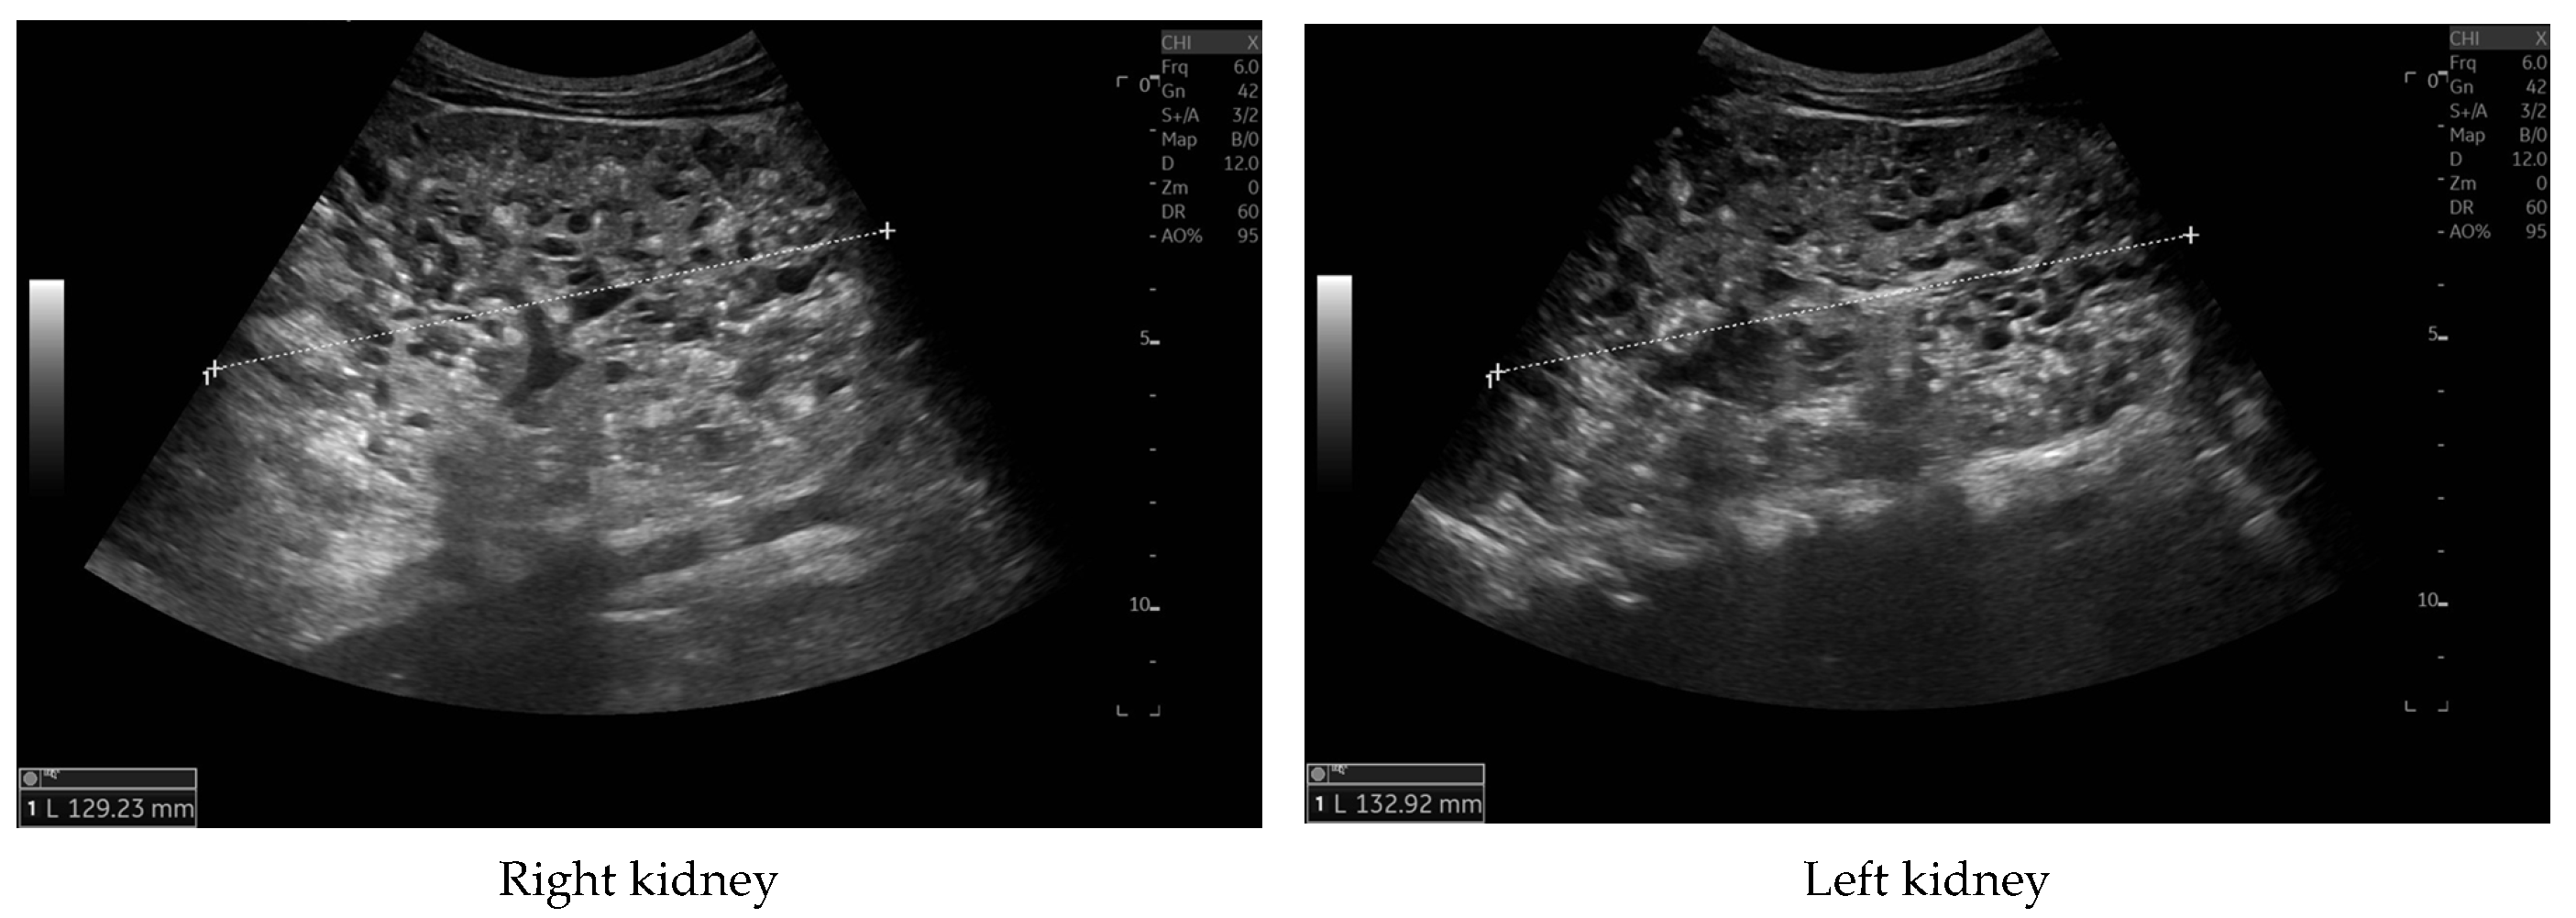

Currently, the boy is 5 years old. The US is similar to the previous one: elevated kidneys length (right: 130 mm (z-score 6.19); left: 133 mm (z-score 6.50)), with increased echogenicity, blurred corticomedullary differentiation, and multiple cysts with a maximum diameter up to 13–15 mm. The liver has a normal size, with numerous cysts up to 16 mm in diameter, with the largest cluster of cysts measuring 43 × 23 × 31 mm (

Figure 3 and

Figure 4). Laboratory tests show increased creatinine 0.79 mg/dL, urea 69,6 mg/dL, cystatin C 1.71 mg/L, uric acid 6.9 mg/dL, urine albumin to creatine ratio (ACR) 118.6 mg/g, and decreased GFR 55 mL/min/1.73 m

2—stage III CKD. Other tests, including electrolytes, liver function, and urinalysis, were normal. The boy demands antihypertensive multi-drug therapy: angiotensin-converting enzyme inhibitors (ACEIs), calcium channel blockers, and beta-blockers.